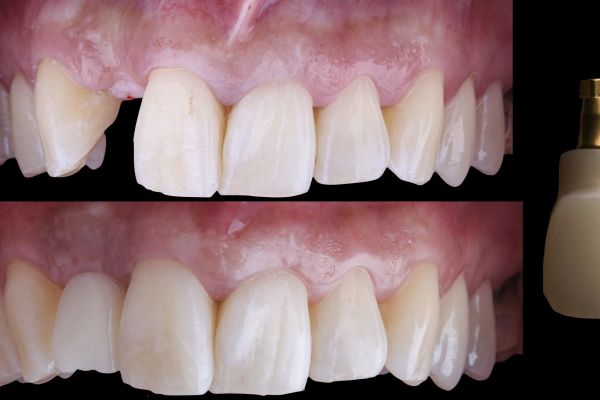

El reto del abordaje quirúrgico en la rehabilitación sobre un implante unitario en un caso de alto requerimiento estético del sector anterior. Descripción a propósito de un caso

Manejo de un defecto estético en maxilar anterior con injertos de tejidos duros y blandos e inserción diferida de un implante dental. A propósito de un caso

The challenge of the surgical approach in the rehabilitation of an anterior sector unitary implant in a case of high aesthetic requirements; case report

Resolución de un caso con implicación estética en el sector antero-superior. A propósito de un caso

Manejo quirúrgico y restaurador de un implante en área estética y evaluación volumétrica tras un injerto de tejido conectivo desepitelizado. Descripción de un caso clínico